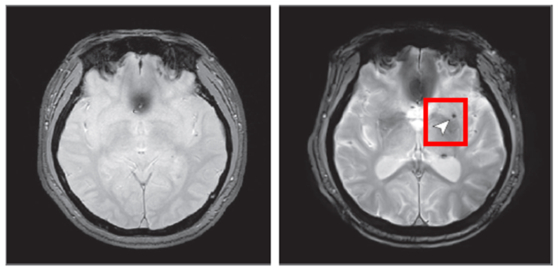

연구팀은 노화 심층조사사업 참여자 1441명을 8년 동안 추적해 수면무호흡증이 뇌 미세출혈 발생에 미치는 영향을 분석했다. 사진은 뇌 미세출혈이 발생하기 전(왼쪽)과 후 한 참여자의 뇌 영상 이미지. 사진 국립보건연구원

분석 결과, 중등도 이상의 폐쇄성 수면무호흡증을 가진 사람은 수면무호흡증이 없는 사람에 비해 뇌 미세출혈이 발생할 위험이 2.14배 증가하는 것으로 나타났다. 반면 경증 수면무호흡증에서는 위험 증가가 관찰되지 않았다. 이런 결과는 뇌혈관 질환 발생 위험과 관련된 특정 유전자(APOE ε4) 보유 여부와는 상관없는 것으로 나타났다. 수면무호흡증이 뇌 미세출혈 발생 위험을 높이는 독립적인 위험 요인이었다는 의미다.